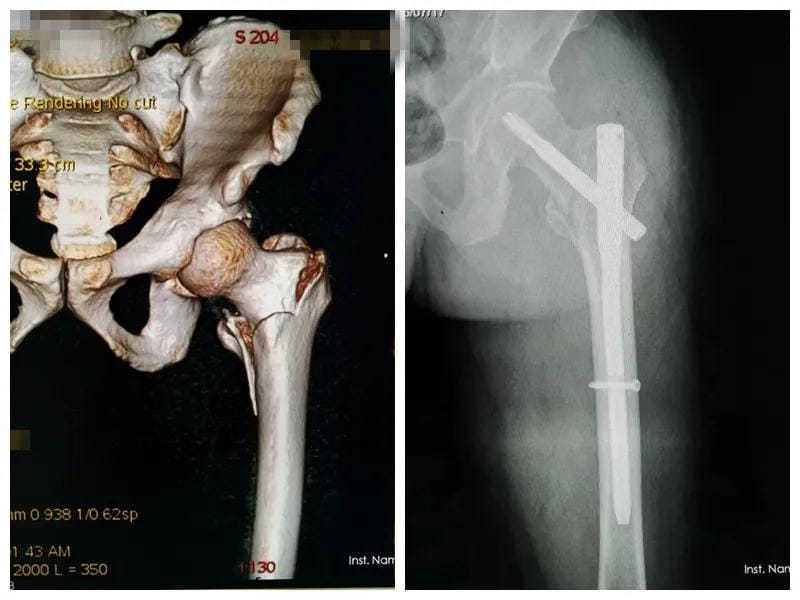

一位十七岁花季少女,因为足踝畸形长期卧床,患者曾先后到广州、昆明、贵阳等地众多知名医院就诊,给出的治疗方案均为截肢手术。家属抱着试试看的态度,到我院骨科门诊就诊,因病例特殊,科室医师经多次讨论,夜以继日设计治疗方案,在与病人及家属三方的共同努力下,通过三次矫形手术,让她终于站了起来,开始享受正常人的生活,不仅找到了工作,现在已经结婚生子,不久前还专程到科室向创伤骨科医护人员表达了谢意,看着她脸上洋溢的幸福,所有的医护人员在为她祝福的同时,也深感了“精治骨伤痛,共结续骨情”的精髓。

矫形、骨髓炎、骨肿瘤:Ilizarov肢体牵拉再生技术,骨延长、肢体延长,各类骨与软组织良恶肿瘤切除术,特别是经典骨巨细胞肿瘤刮除植骨骨水泥填充内固定术、四肢恶性骨肿瘤保肢术+新辅助化疗方案等标准化治疗等。